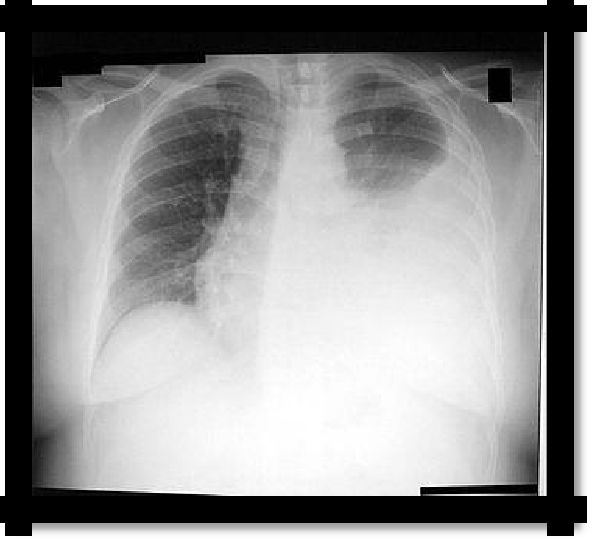

1. X-ray homogeneous dimming is determined in the lower part of the pulmonary field with a characteristic oblique upper border for exudate and a more horizontal upper border for transudate. In the latter case, the process is often two-way. There is a shift in the mediastinal organs to a healthy side.

Pic 2.4 The line of Damoiso-Ellis-Sokolov (1); The Garland Triangle (2)

and the Rauchfus-Grocco Triangle (3) with exudative pleurisy.

Pic 2.5 Left-

sided exudative pleuritis